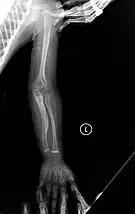

- Type V – Having the same clinical features as type IV, it can be clinically distinguished by observing a "mesh-like" appearance to a bone biopsy under a microscope. Type V can be further distinguished from other types of OI by the "V triad": an opaque band (visible on X-ray) adjacent to the growth plates; hypertrophic calluses (abnormally large masses of bony repair tissue) which form at fracture sites during the healing process; and calcification of the interosseous membrane of the forearm,[50] which may make it difficult to turn the wrist.[1]: 429 Other features of this condition may include pulled elbow, and, as in other types of OI, long bone bowing and hearing loss.[64] Cases of this type are caused by mutations in the IFITM5 gene on chromosome 11p15.5.[64][49] The separation of type V from type IV OI, its clinical type, was initially suggested even before its genetic cause was known, by Glorieux et al. in 2000.[50][65] Type V is relatively common compared to other genetically defined types of OI—4% of OI patients at the genetics department of the Brazilian Hospital de Clínicas de Porto Alegre were found to have it.[66]

Diagnosis is typically based on medical imaging, including plain X-rays, and symptoms. In severe OI, signs on medical imaging include abnormalities in all extremities and in the spine.[97] As X-rays are often insensitive to the comparatively smaller bone density loss associated with type I OI, DEXA scans may be needed.[5]: 1514